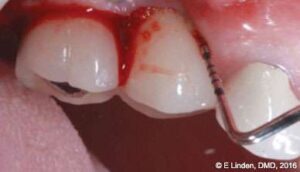

Laser procedure: First, the crest epithelium was removed (SuperPulse laser settings) outside the peri-implant pockets in order to vaporize bacteria and to delay the down growth of epithelium into the pocket. Then the laser perio tip was introduced into the peri-implant pocket. The tip was backed off to maintain 1 mm-2 mm “safety margin” from the depth of the pocket. The tip was slowly moved sideways circumferentially the full width of the pocket (Figure 9A). Then the tip was brought up 1 mm, and another circumferential stroke was made, 1 mm up — and another circumferential stroke — until the top of the pocket was reached. The hand speed is crucial for this procedure: It should be slower — approximately 1 mm/sec for thicker epithelium — and slightly faster for thinner epithelium — approximately 2-3 mm/sec.

Hemostasis: The laser was then reintroduced into the peri-implant pockets with the coagulation settings. Laser energy was used to coagulate the blood and cause formation of a clot that would slow down epithelial migration inside the pocket. The laser coagulation technique is similar to the de-epithelialization one described above, when the laser tip was moved circumferentially with approximately 1 mm/sec hand speed for strongly bleeding blood vessels (to cause 0.3 mm deep coagulation) and approximately 2-3 mm/sec for blood vessels that were bleeding less profusely.

Follow-up examination: The patient returned for the first follow-up examination at 1 week postoperatively (Figures 10A-10C). The healing progressed well, and no signs of swelling or inflammation were present. During follow-up examination at 6 months postoperatively, the treatment site was completely healed with no signs of periimplantitis (Figures 11A-11C). The pocket depth, measured during the 6-month postoperative visit, was reduced to 3 mm-4 mm. (Significant improvement in comparison with the initial probing depths of up to 9 mm.)